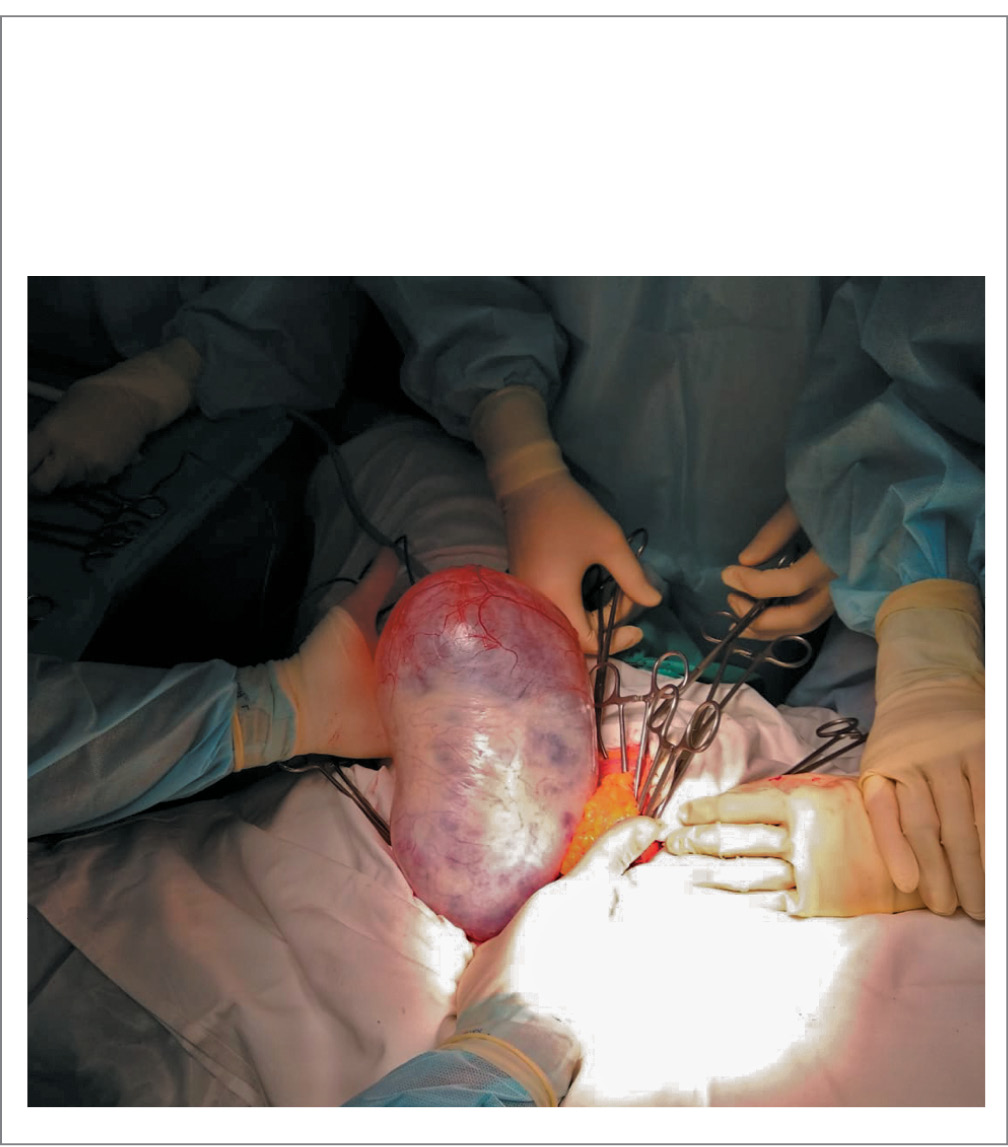

Рис. 2. Киста яичника при правосторонней аднексэктомии (первый этап операции).

Fig. 2. Ovarian cyst in right-sided adnexectomy (first stage of surgery).

Первым этапом выполнена нижне-средне-срединная лапаротомия. Выявлено: в брюшной полости объемное жидкостное образование, исходящее из правого яичника, размерами 26×15×16 см, неспаянное с окружающими тканями, наружная поверхность капсулы образования гладкая, без видимых папиллярных разрастаний. Правая маточная труба распластана по жидкостному образованию. Правая воронко-тазовая связка и собственная связка яичника, маточная труба пережаты, пересечены и лигированы викриловым швом. При осмотре органов брюшной полости другой видимой патологии не выявлено.

После удаления образования из брюшной полости выявлено: левые придатки и матка пролабируют за пределы малого таза и не вправляются в брюшную полость. Выполнено типичное удаление большого сальника, гемостаз по ходу удаления производился с помощью биполярного зажима LigaSure LF4318 (Covidien, США), состоятелен. На рис. 2 представлен этап извлечения кисты правого яичника.